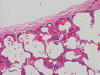

At scanning magnification (Panel A), the lung parenchyma is replaced by some coalescing fibrous nodules. The degree of involvement is variable at different fragments (Panel B and C). In the less affected areas, there are some fibrotic thickening of the septa (Panel C). In some areas, the changes are minimal and the pleural appear to be uninvolved (Panel D and E). In low to medium magnifications, these nodules of fibrosis contains a large number of hemosiderin laden macrophages (Panel F and G) admixed with fibrous tissue. The diagnostic tissue, however, is present in areas with increased cellularity. In these areas, there is a background of cells with a moderate amount of cytoplasm and bland nuclei. Some of these nuclei have kidney shape (arrow in Panel H). In some areas, many of the nuclei have a deep nuclear groove that resemble a coffee bean (arrow in Panel I). In the third type of areas, the nuclear grooving is not distinct (Panel J). Prominent eosinophilic infiltrations are almost always present. Immunohistochemistry on CD1a revealed many positive cells (Panel L). Also present in the specimen are multiple small blood vessels with thickened intima (Panel K). A Movat pentachrome stain demonstrates an internal elastic layer in these vessels and confirms that these are arteries (Panel M and N).